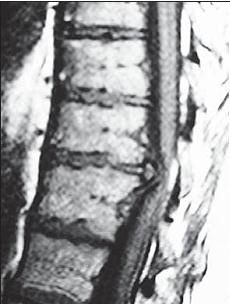

На серии снимков МРТ № 24 наблюдаются дорсальные грыжи межпозвонковых дисков в поясничном отделе позвоночника в сегментах Lv—SI Это самый уязвимый межпозвонковый диск, так как в силу своего анатомического расположения на него приходятся самые большие нагрузки. Как говорится, по счёту «последний», а по уязвимости, первый. Поэтому в нём чаще, чем в других межпозвонковых дисках, возникают, различные осложнения, в том числе и грыжи МРТ № 25

На серии снимков МРТ № 25 наблюдаются дорсальные грыжи межпозвонковых дисков в поясничном отделе позвоночника в сегментах LIV-LV Lv—SI Такие комбинации, в которых образуются по нескольку грыж, межпозвонковых дисков одновременно, случаются довольно часто на более поздних стадиях развития дегенеративно-дистрофического процесса. В общем, беда не приходит одна, «несчастье» любит, компанию МРТ № 26